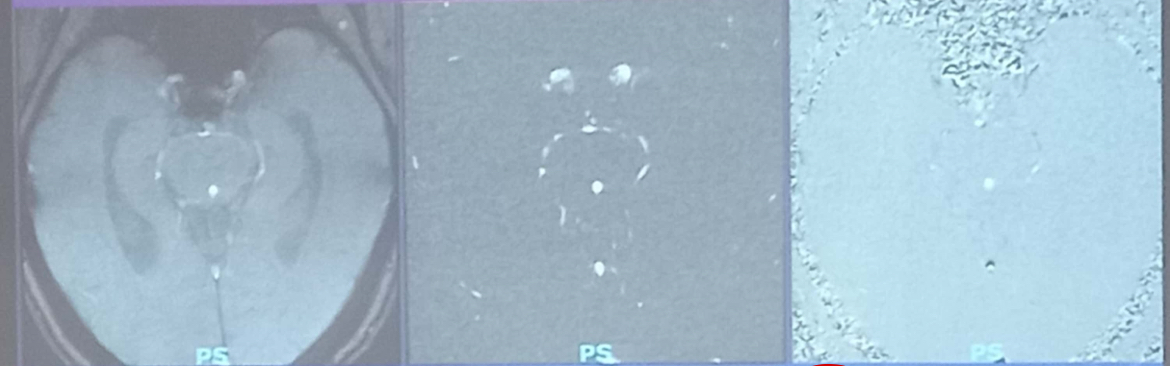

Gọi tên các hình ảnh sau

Rephased image: dòng chảy tín hiệu cao, ch xoá nền

→ GP

Magnitude sum: dòng chảy có tín hiệu cao, xoá nền

→ mạch máu

Phase image: tín hiệu dòng chảy phụ thuộc vào hướng, tín hiệu nền tb

→ vận tốc và hướng chảy